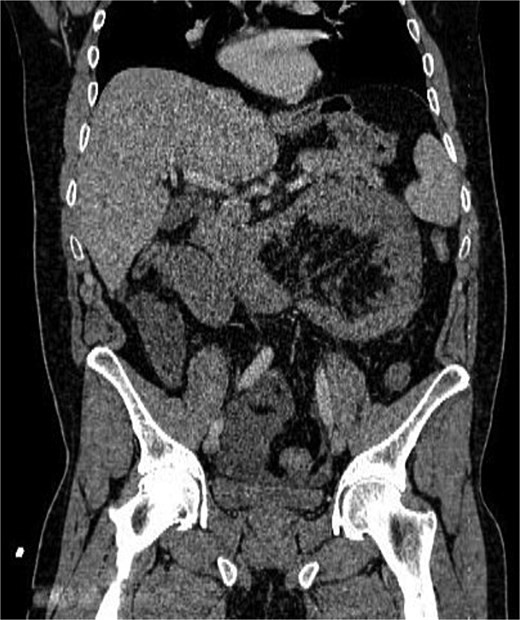

أظهرت الفحوصات والتصوير الطبي وجود فتق داخلي نادر أدى إلى احتباس جزء من الأمعاء الدقيقة داخل تجويف غير طبيعي في البطن، ما تسبب في انسدادها وانقطاع التروية الدموية عنها.

ويُعد هذا النوع من الحالات من الأسباب النادرة لانسداد الأمعاء، لكنه قد يتحول بسرعة إلى حالة مهددة للحياة إذا لم يتم التدخل الجراحي العاجل.